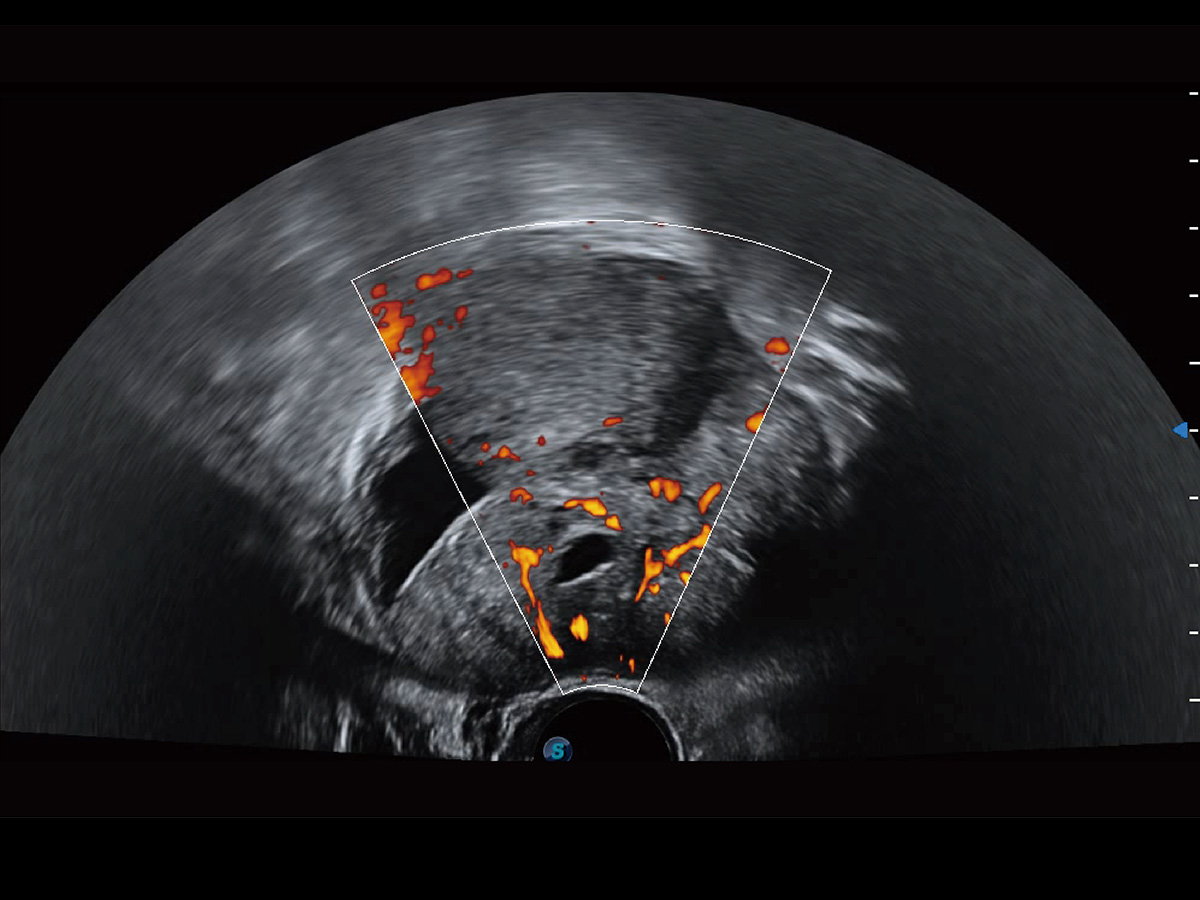

“生育问题”即关系民族复兴,也关系亿万家庭的幸福。随着婚育年龄推迟、社会压力增加等因素,越来越多人群也面临着“生不出、生不好”的问题。辅助生殖作为治疗不孕不育最有效的方法之一,也逐渐成为育儿新希望。而超声检查能为生殖需求人群的初诊评估提供宝贵的信息。 P20 Elite是开立医疗匠心打造的一款生殖应用型彩超。她继承开立医疗高端极光平台,突破性地将多款新型芯片及硬件模块进行整合,均衡了高端系统性能与小巧灵动机身。P20 Elite卓越的图像质量搭载专科探头,旨在为您提供全面的辅助生殖解决方案。

P20 Elite配备了丰富的生殖探头群和临床应用功能,在卵泡监测、穿刺取卵、胚胎移植、妊娠确认等领域,为生殖需求人群提供了新的临床机会,重新定义高端超声如何应用于生殖健康检查。